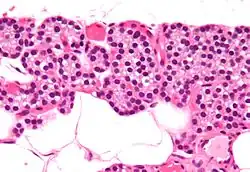

Micrografia ampliada com coloração H&E, mostrando as células (escuras) chefes que segregam os hormônios das paratiroides.

Histologicamente, as paratiroides apresentam dois tipos de células: as principais e as oxifílicas. As células principais são menores e abundantes, e são elas que secretam a PTH. As células oxífilicas são maiores, mais eosinófilas (devido à sua abundância de mitocôndrias) e têm função desconhecida. Cada glândula é envolvida por uma cápsula própria, da qual se projetam feixes de tecido conjuntivo que dividem o interior da glândula em lóbulos.

Os dois tipos de células, principais e oxífilicas, são sustentadas por uma matriz de tecido conjuntivo reticular e adiposo.

Células oxifilas em coloração por hematoxilina e eosina,apresentam o seu núcleo intensamente corado pela hematoxilina,enquanto que seu citoplasma homogeneo e corado pela eosina,estas células não secretam PTH,a função celular é desconhecida

As células principais,apresentam núcleo densamente corado e o citoplasma também intensamente coradas, estas células são responsáveis pela secreção do hormônio Paratormônio(PTH).As células principais,normalmente se apresentam como uma coloração mais escuras,o que denota uma atividade nuclear e enzimática ativas,enquanto que as células claras, são denominadas assim por serem células principais em repouso,em que não é observado a produção de PTH,mas no seu citoplasma tem acumulo de lipídeos e glicogênio.